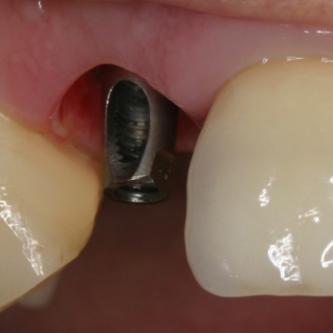

Exemple 3: Un implant à la place d'une incisive latérale supérieure droite. Sur cette image on voit le moignon en titane qui est vissé sur l'implant.

Exemple 3: Puis sur ce moignon, la couronne en céramique est scellée.

Exemple3: La couronne en place.